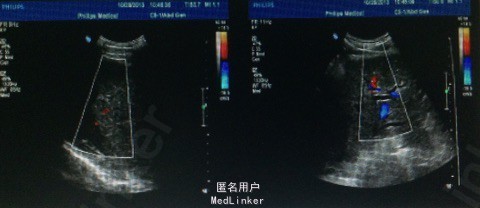

辅助检查: 2013-10-16市中心医院CT提示,肝脏右叶大片低密度影 2013-10-22市中心医院胃镜1、中度食管静脉曲张,2、慢性浅表性胃炎;直肠 炎。 肝功能谷丙转氨酶22U/L,谷草转氨酶49U/L,白蛋白33.5g/L。总胆红素23.1 umo1/L,直接胆红素8.20 umo1/L。乙肝病毒(HBV-DNA) 3.13×103。 腹部超声:1.肝内巨大实质性肿块并肝左叶胆管扩张,2.肝硬化、脾肿大。